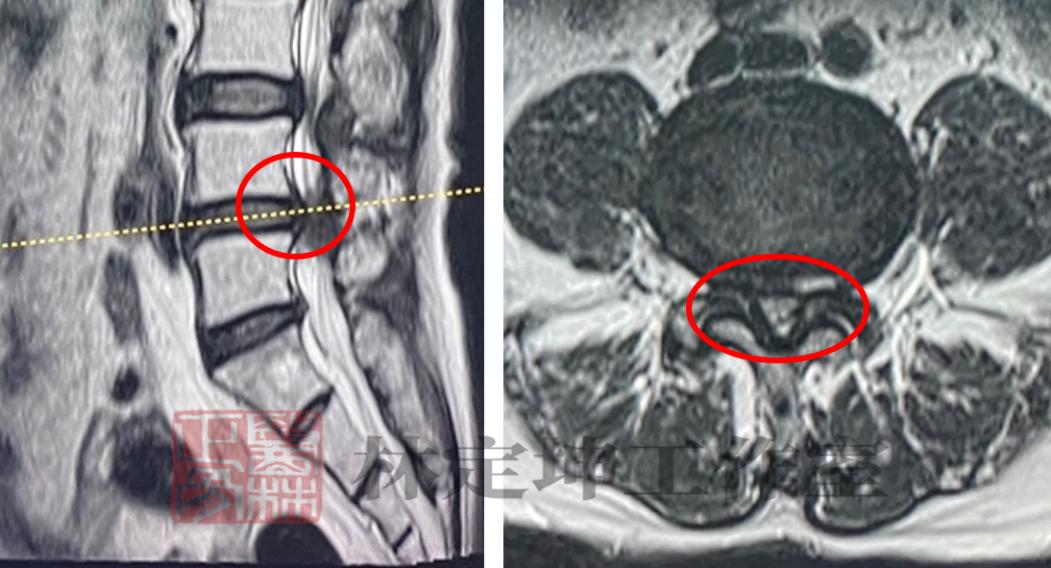

▲核磁共振检查结果显示陈奶奶存在腰椎管狭窄的情况

经过核磁共振检查发现,影像显示陈奶奶存在腰椎管狭窄的情况,属于 退变性腰椎管狭窄症 。而这正是导致陈奶奶 长期腰腿疼痛 的元凶。